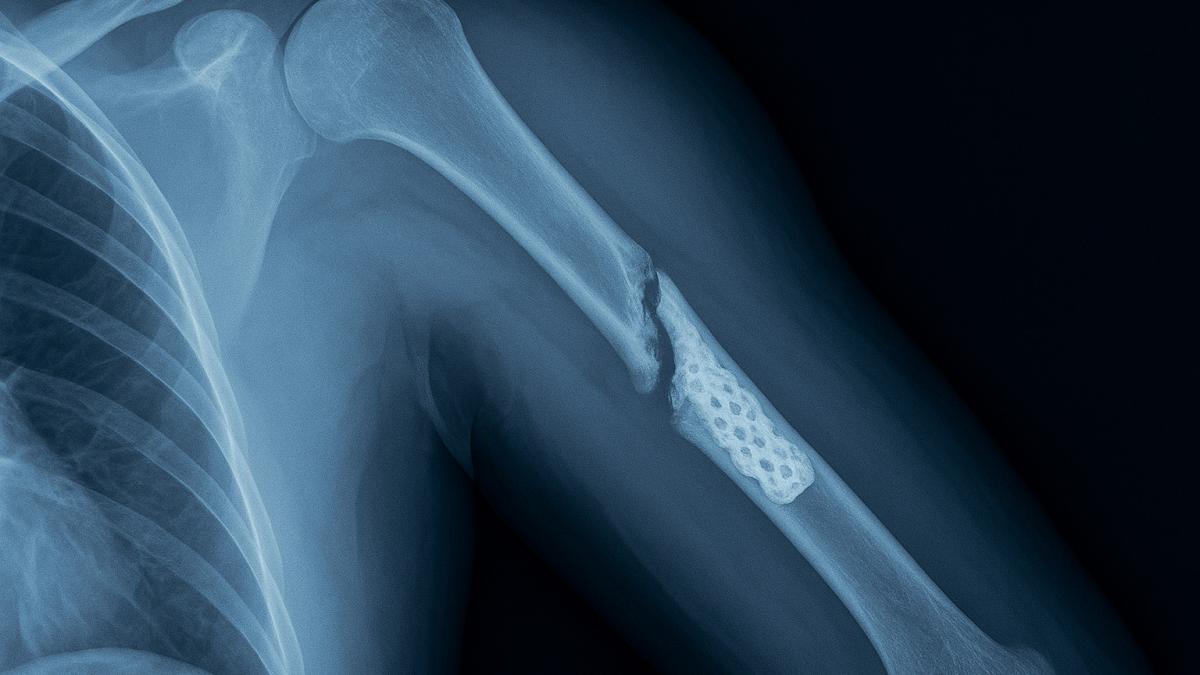

Рентген с 3D-имплантатом

В 2024 году международная группа исследователей представила инновационный имплантат на основе крови, способный усиливать естественные механизмы восстановления костной ткани. Его назвали "биокооперативным регенеративным" материалом. Он создан на основе синтетических пептидов и воспроизводит природные процессы, происходящие в организме при заживлении ран.

В ходе испытаний на крысах материал показал впечатляющие результаты: гелеобразное вещество, совместимое с 3D-печатью, стимулировало рост костей и ускоряло заживление переломов.

"Возможность легко и безопасно превращать кровь людей в высокорегенеративные имплантаты действительно впечатляет", — отметил биомедицинский инженер Козимо Лигорио из Ноттингемского университета.

Ключевое преимущество этой технологии заключается в доступности: кровь можно получить от самого пациента, что снижает риск отторжения и делает лечение дешевле и безопаснее.